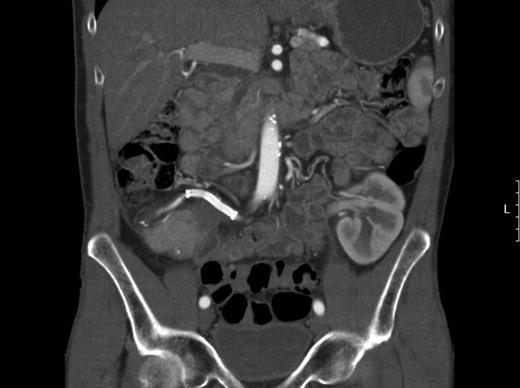

Because of the patient’s stability and desire to keep his well-functioning pancreatic graft, a close-monitoring policy was followed and the graft was left in place. Several follow-up CT angiographies showed no sign of endoleak or recurrent aneurysm (Fig. 4). Vitamin K antagonists were stopped and replaced with acetyl salicylic acid prophylaxis. After 12 months of follow-up, the patient is still well with excellent kidney and pancreas graft function.

Follow-up CT scan showing a patent SMA tract with stent in position and no signs of endoleak.